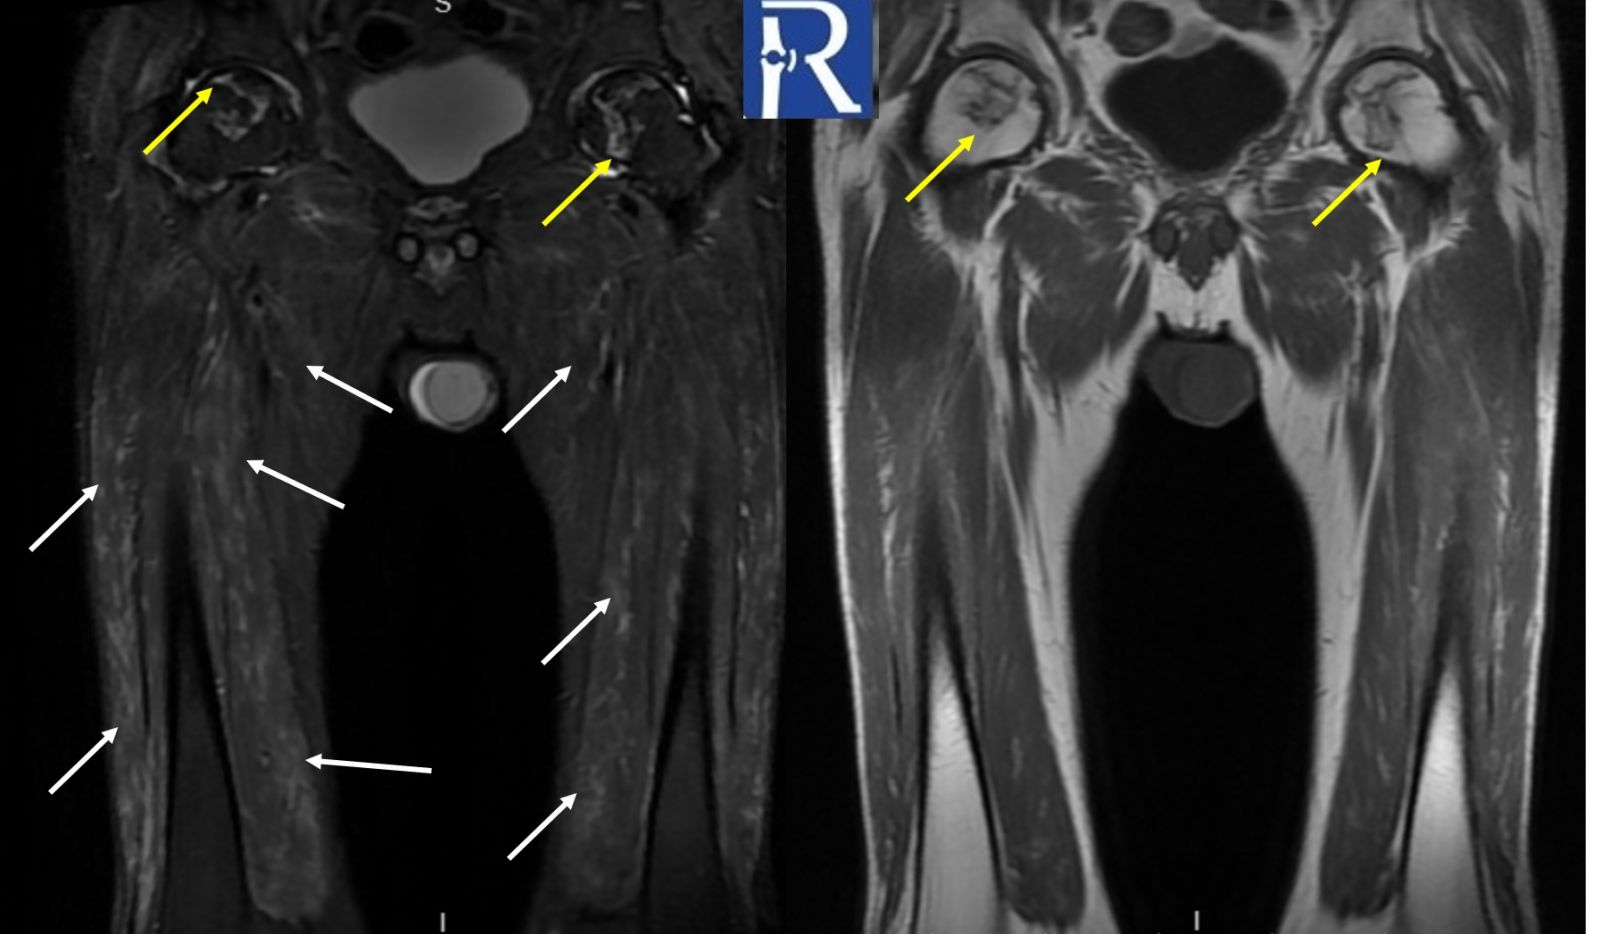

MRI Findings:

MRI of the both thigh reveals bilateral crescent-shaped, geographic lesions in the femoral heads consistent with osteonecrosis (formerly avascular necrosis) (yellow arrows). Additionally, there are bilateral, symmetrical, heterogeneous hyperintense signal changes—resembling edema—predominantly affecting the anterior muscle groups of the thighs (white arrows), indicative of myositis. There is also diffuse loss of subcutaneous fat tissue with focal areas of mildly increased T2 signal (red arrow).